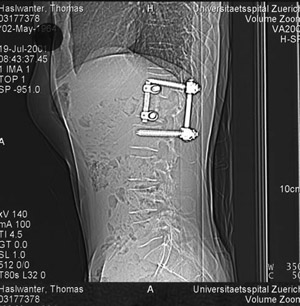

Ironically, after climbing in the mountains for 17 years, my accident happened in a climbing gymn. On April 25 2001, over lunch in a climbing gymn, Sarah missunderstood me, and - instead of lowering me - she disengaged the rope. I fell 12 m, backward. The impact shattered my top lumbar vertrebra, compressing my spinal cord. They got me into hospital fairly quickly. Jean, my wife, was told I’d be in a wheelchair. I wasn’t - but only by 1 mm of nerve fibers, which survived the accident ….